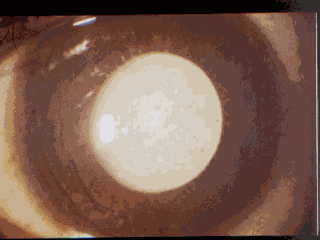

Congenital cataract: the epidemic that led to the discovery of the rubella syndrome